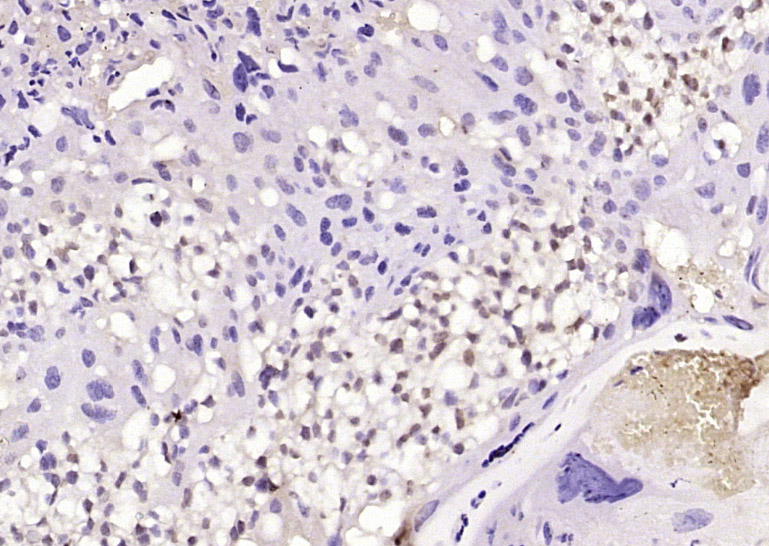

Paraformaldehyde-fixed, paraffin embedded (mouse heart tissue); Antigen retrieval by boiling in sodium citrate buffer (pH6.0) for 15min; Block endogenous peroxidase by 3% hydrogen peroxide for 20 minutes; Blocking buffer (normal goat serum) at 37°C for 30min; Antibody incubation with (PHD3) Polyclonal Antibody, Unconjugated (bs-0532R) at 1:400 overnight at 4°C, followed by operating according to SP Kit(Rabbit) (sp-0023) instructionsand DAB staining.

Paraformaldehyde-fixed, paraffin embedded (mouse placenta tissue); Antigen retrieval by boiling in sodium citrate buffer (pH6.0) for 15min; Block endogenous peroxidase by 3% hydrogen peroxide for 20 minutes; Blocking buffer (normal goat serum) at 37°C for 30min; Antibody incubation with (PHD3) Polyclonal Antibody, Unconjugated (bs-0532R) at 1:400 overnight at 4°C, followed by operating according to SP Kit(Rabbit) (sp-0023) instructionsand DAB staining.